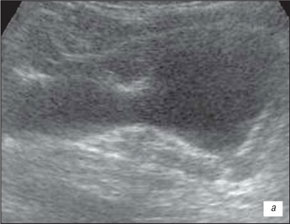

Ехограма розширення порожнинної системи нирки

А – розширення сечоводу:

Б – на тлі сечового міхура.

1 – сечовий міхур, 2 – сечовід

На даній ехограмі спостерігається: зменшення розмірів нирки на стороні поразки; циклічна зміна діаметру сечоводу у верхньому і нижньому відділах; вертикальну спрямованість сечовідно-міхурного викиду, який в нормі має напрям під кутом 30–40° по відношенню до умовної лінії, що сполучає гирла сечоводів.